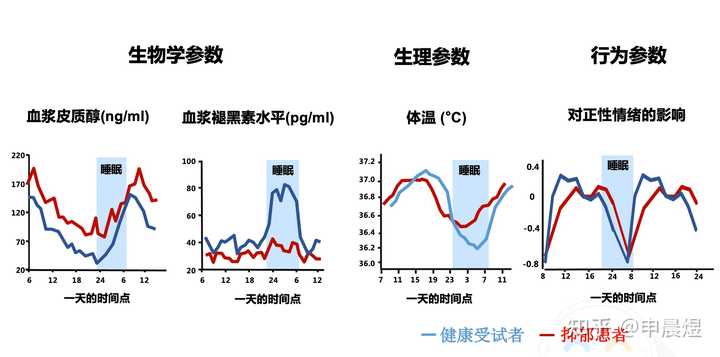

也称为“生物钟”,是机体内部发生的周期性变化过程,最典型的例子是睡眠与觉醒的周期性交替。昼夜节律(circadian rhythms) 是生物节律之一,是有机体在生物钟控制下产生的生物化学、生理学、行为模式的24h循环周期[1]。大多数生理和行为是由下丘脑生物钟控制的,分子钟作用于神经和内分泌通路,调节个体的生物节律,使机体在24h内适应外部环境的改变,并通过合成代谢和分解代谢来提高机体运转的效率[2]。

生物节律紊乱使抑郁症风险升高

睡眠和生物节律紊乱(SCRD)是21世纪普遍特征,对轮班工人的研究表明,SCRD不仅导致认知障碍,还会导致代谢综合征和抑郁症等精神障碍[3]。

生物节律紊乱引发的睡眠障碍持续存在,可导致抑郁复发风险增高[4]。

与昼夜节律正常的同龄人相比,节律延迟的个体抑郁症状更严重,且更易出现轻度躁狂症状[5]。

抑郁症可致生物节律相位延迟

抑郁患者的生物节律往往是相位延迟的,意味着早上觉醒度不足,晚上入睡困难。难以入睡进一步加剧了白天的困倦感[7]。

抑郁症患者的睡眠结构节律紊乱[8]